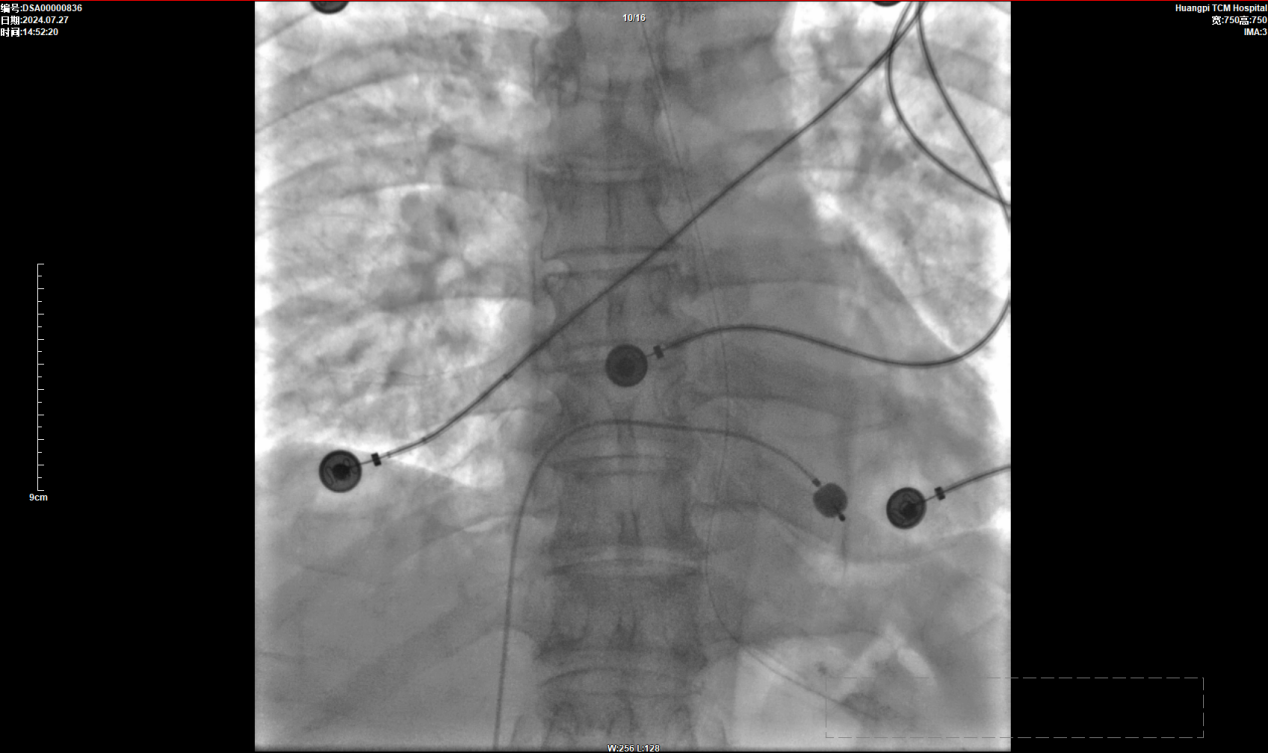

经与家属充分交代病情取得同意后,在心血管病科团队和介入室团队的共同努力下,在介入导管室内成功为患者植入了心脏临时起搏器。术后心电图示心室起搏节律,心率50次/分,患者术中、术后无任何不良反应,待患者生命体征平稳后即返回原病房继续行术后相关治疗。